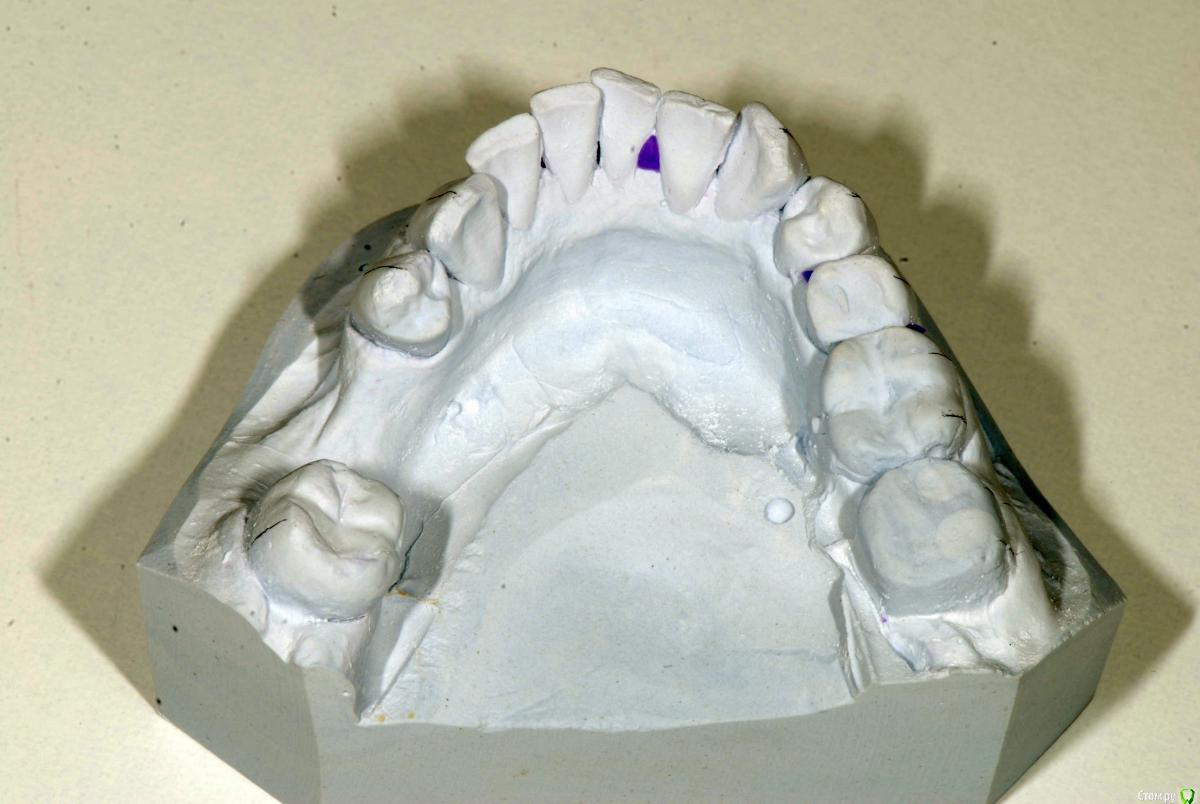

krokomot Опубликовано 12 декабря, 2016 Поделиться Опубликовано 12 декабря, 2016 Вот именно в чем в принципе сомневаетесь? и на моделях надо указывать анатомический центр, тогда сразу понятнее станет чего и куда и на сколько. Ссылка на комментарий

Afffinity Опубликовано 13 декабря, 2016 Автор Поделиться Опубликовано 13 декабря, 2016 Вот именно в чем в принципе сомневаетесь? и на моделях надо указывать анатомический центр, тогда сразу понятнее станет чего и куда и на сколько. ну Вы хотя бы свои мысли озвучили бы, расчет трг, характер асимметрии (в каком положении головки, что на КТ?) ... полностью Вам не распишут план, вопросы более конкретные попробуйте задать для коллегЕсли кратко то по расчетам ТРГ 2й скелетный класс, в цифрах завтра распишу. Прошу прощения что сразу не выложил. 2е, смущает смещение центральной линииПланируем установить систему Damon Q. Самый главный вопрос, возмножо ли в данном случае обойтись без удаления премоляров? Ссылка на комментарий